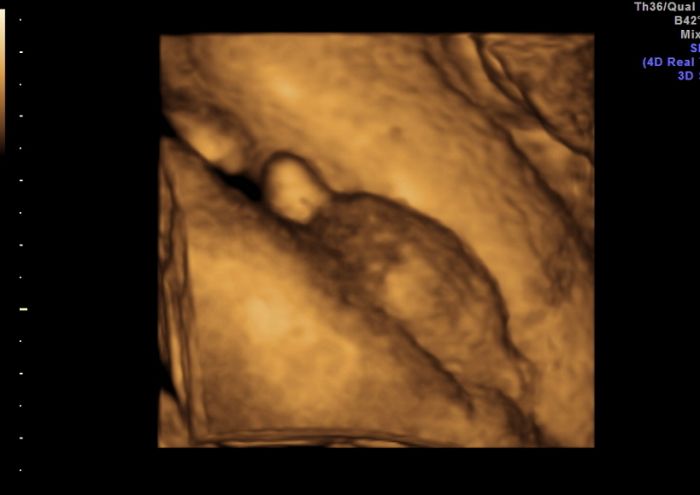

Já je přikládám

pindíka našeho

a na druhé a třetí fotce má před pusinkou pupečník, ale usmíval se na nás šmudlík malej náš